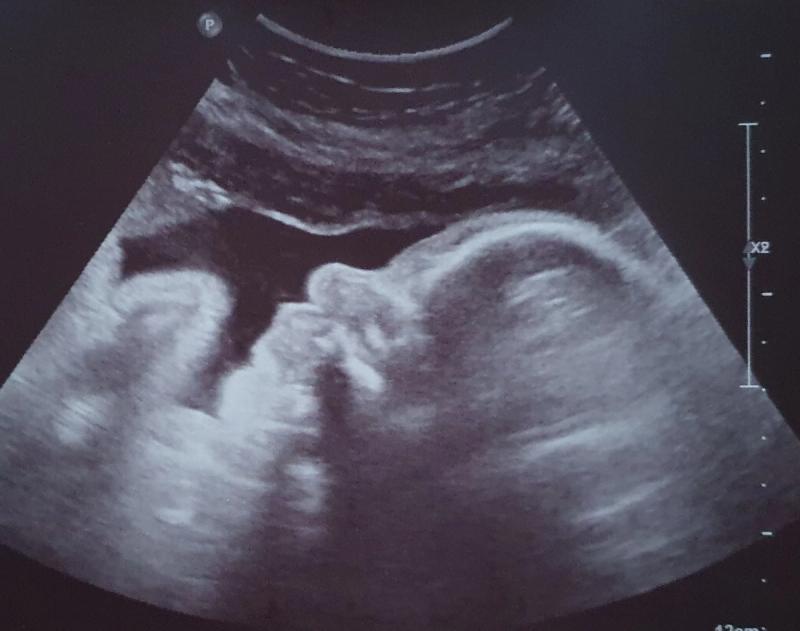

Vanaf dat moment kon ik nog alleen maar lachen. De weken vlogen voorbij en ook de 12 weken echo was goed. 29 augustus 2020 zou de datum zijn waar we naar uit mochten kijken en alles was goed. Iedereen mocht het weten en met de 20 weken echo wilden we weten wat het geslacht zou zijn. Dit werd al snel duidelijk, we kregen een dochter. Wat waren wij blij en alles was nog steeds goed. De weken vlogen voorbij, de buik groeide goed en ik pronkte er graag mee.

Ons meisje bleek aan de te kleine kant

Tot het een dag voor moederdag was en ik minder leven voelde. Ik belde wat onzeker de verloskundige en gaf aan dat het vast niks was, maar me toch wel zorgen maakte. De verloskundige kwam meteen langs. We hoorden een hartslag en mijn bloeddruk was goed. Ik was pas 24 weken dus dan kan het vaker voorkomen dat ze even wat rustiger zijn of anders liggen. Uit voorzorg werden we wel doorgestuurd naar het ziekenhuis voor een CTG en een echo. Eenmaal in het ziekenhuis maakten wij ons geen zorgen meer, want we hadden immers een hartslag gehoord. De CTG was goed, wel had de kleine een hoge hartslag en daarna kwam de echo. Tijdens de echo hoorden we dat er goede kindbewegingen waren, dus weer hadden we geen zorgen meer. Maar er werd wel gezegd dat ze aan de kleine kant was, haar beentje zit op de P6 lijn en P50 zou gemiddeld zijn. Dit was niet goed en ik moest de vrijdag erna terug komen voor een controle bij de gynaecoloog. Door Corona moest ik alleen komen en mocht mijn man helaas niet mee.

De gynaecoloog zei dat mijn man moest komen

Het was vrijdag 15 mei 2020 en ik ging naar de controle bij de gynaecoloog in het ziekenhuis. Vol goede moed ging ik erheen, want ik ben zelf ook klein dus maakte me al geen zorgen meer. “We krijgen gewoon een kindje wat niet zo groot is”, zei ik tegen mijzelf. Er werd een nieuwe groei-echo gemaakt. Hier werd verteld dat ze drie weken achter lag in groei. En dit was vreemd want tot de 20 weken echo groeide ze nog gewoon gemiddeld. De moed zakte in mijn schoenen en langzaam kreeg ik paniek. Er werd ook een dopplermeting gedaan (de doorbloeding van de navelstreng wordt dan gemeten). Ik kreeg te horen dat ik weer mocht gaan zitten en dat ze even alles in de computer ging zetten. Dit duurde voor mijn gevoel lang, heel lang… Vervolgens zei de gynaecoloog dat de dopplermeting niet goed was en dat het verstandig was dat mijn man direct zou komen. Ik werd doorgestuurd naar de afdeling en de kans was aanwezig dat ik werd opgenomen.